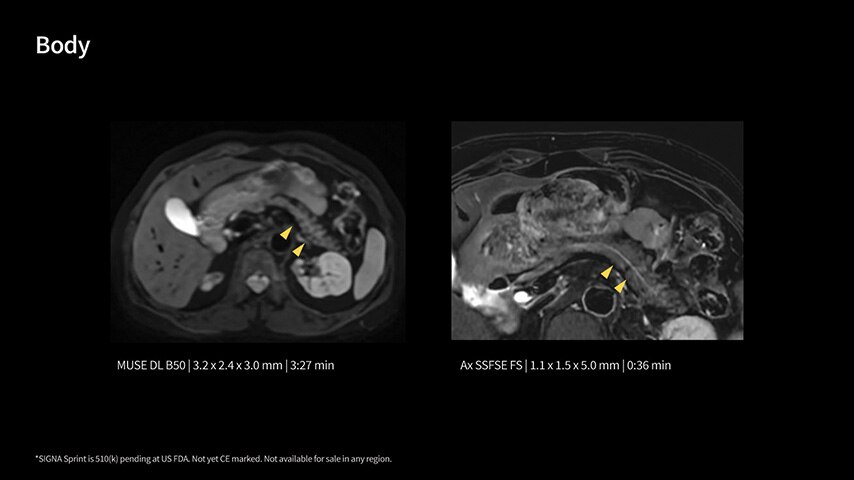

In oncological assessments, diffusion imaging is a critical clinical indicator. SIGNA Sprint offers clearer diffusion, reduced distortion, and improved SNR.¹

Within cardiovascular diseases, the functional assessment of the heart is an essential imaging application. SIGNA Sprint is powered by built-in AI technologies—Sonic DL™, AIR Recon DL and AIR x™—enabling high-quality imaging even in the most demanding anatomies.